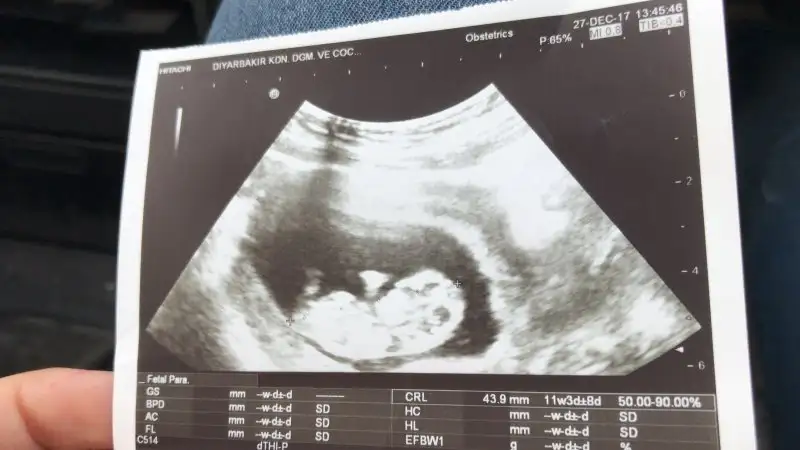

bebegin7-8 haftalıkkenki usg resimine direkt baktıgınızda;

bebek kesenin soluna yakınsa bebek erkek,

sagına yakınsa kız.

Mrb bende 9haftalık hamilymBu yöntem bircok kişide dogru sonuc verdii.

Biri 7 hafta 1 günlük biri 11 haftalık şuan 13 haftalık oldum acaba cinsiyeti ne olabilir tahmin de bulunabilir misiniz acaba Haftaya da doktora gidip net bi şekilde öğrenicem inşallah[/QU